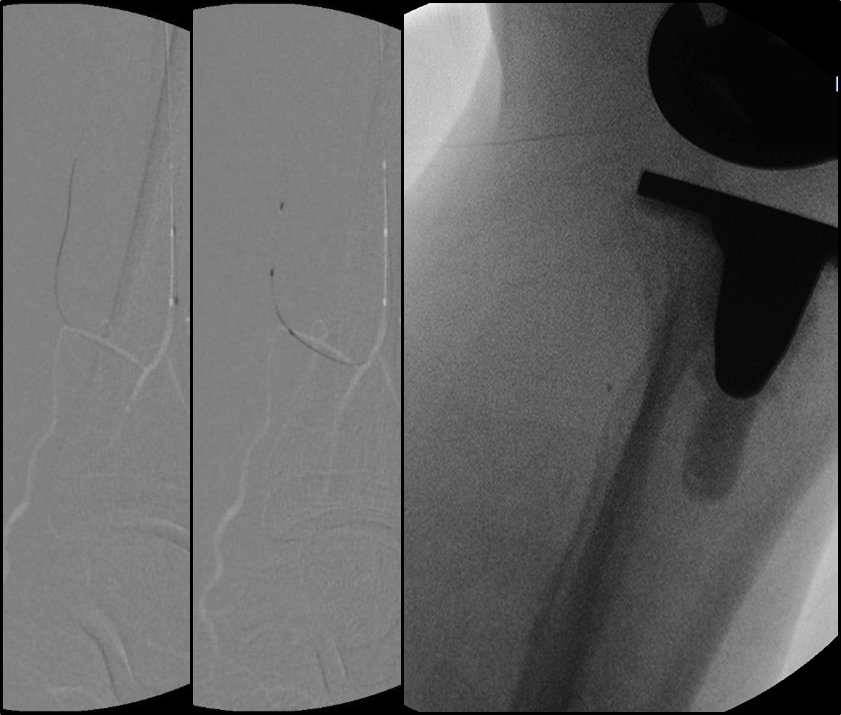

BTK 标准化开通流程

Ante-True Lumen

Fail + short lesion

Fail →Retro puncture

Fail → SAFARI/CART/r-CART

Fail + long lesion

Fail → PA/PTA

Fail → ATA

Fail → PCA

Fail → Puncture

Fail → Pedal arch

Antegrade access with retrograde wireguided